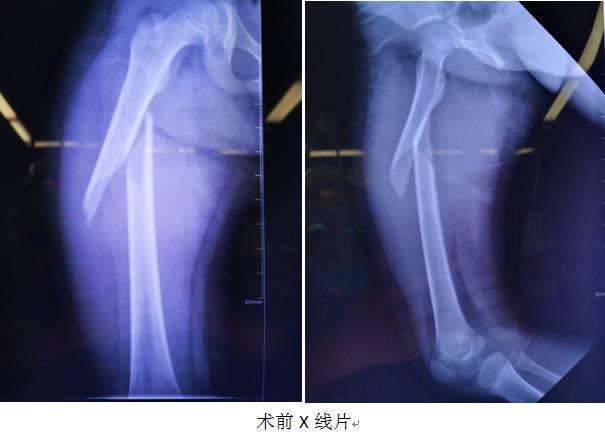

近日,骨二科急诊完成了一例小儿股骨干骨折闭合复位弹性髓内钉固定术。

6岁患儿因股骨干骨折入院,医师张建接诊患者,为患者量身定制了手术方案。手术全程在C型臂引导下,仅在骨折远端(近端)内外侧各做一长约1.5cm切口(此例手术总共两个切口),选择合适直径的弹性髓内钉自骨折远端(近端)置入髓腔,通过骨折断端到达对侧并使骨折复位,待3-6月后骨折愈合后再经原切口取除弹性髓内钉。